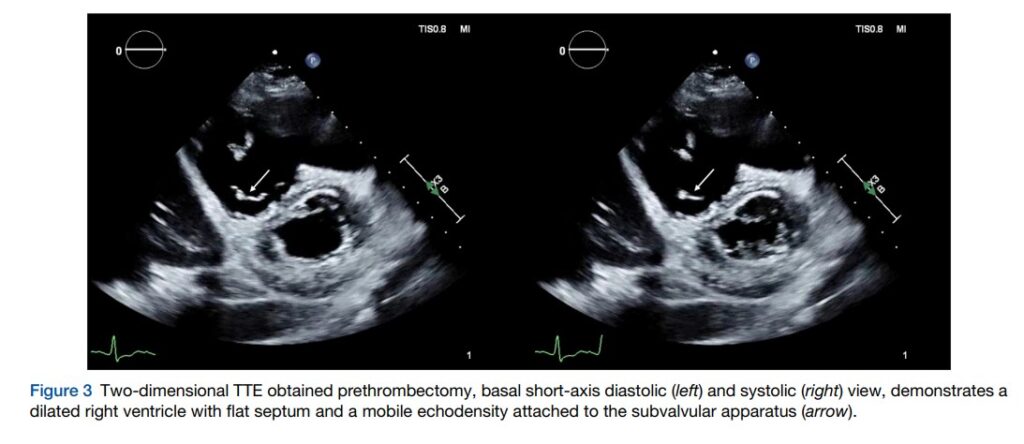

A pressão sistólica da artéria pulmonar (PSAP) foi estimada em 43 mmHg. Ainda, havia regurgitação tricúspide moderada. Um trombo em trânsito foi aventado pela presença de uma imagem ecogênica móvel observada no aparato subvalvar tricúspide.